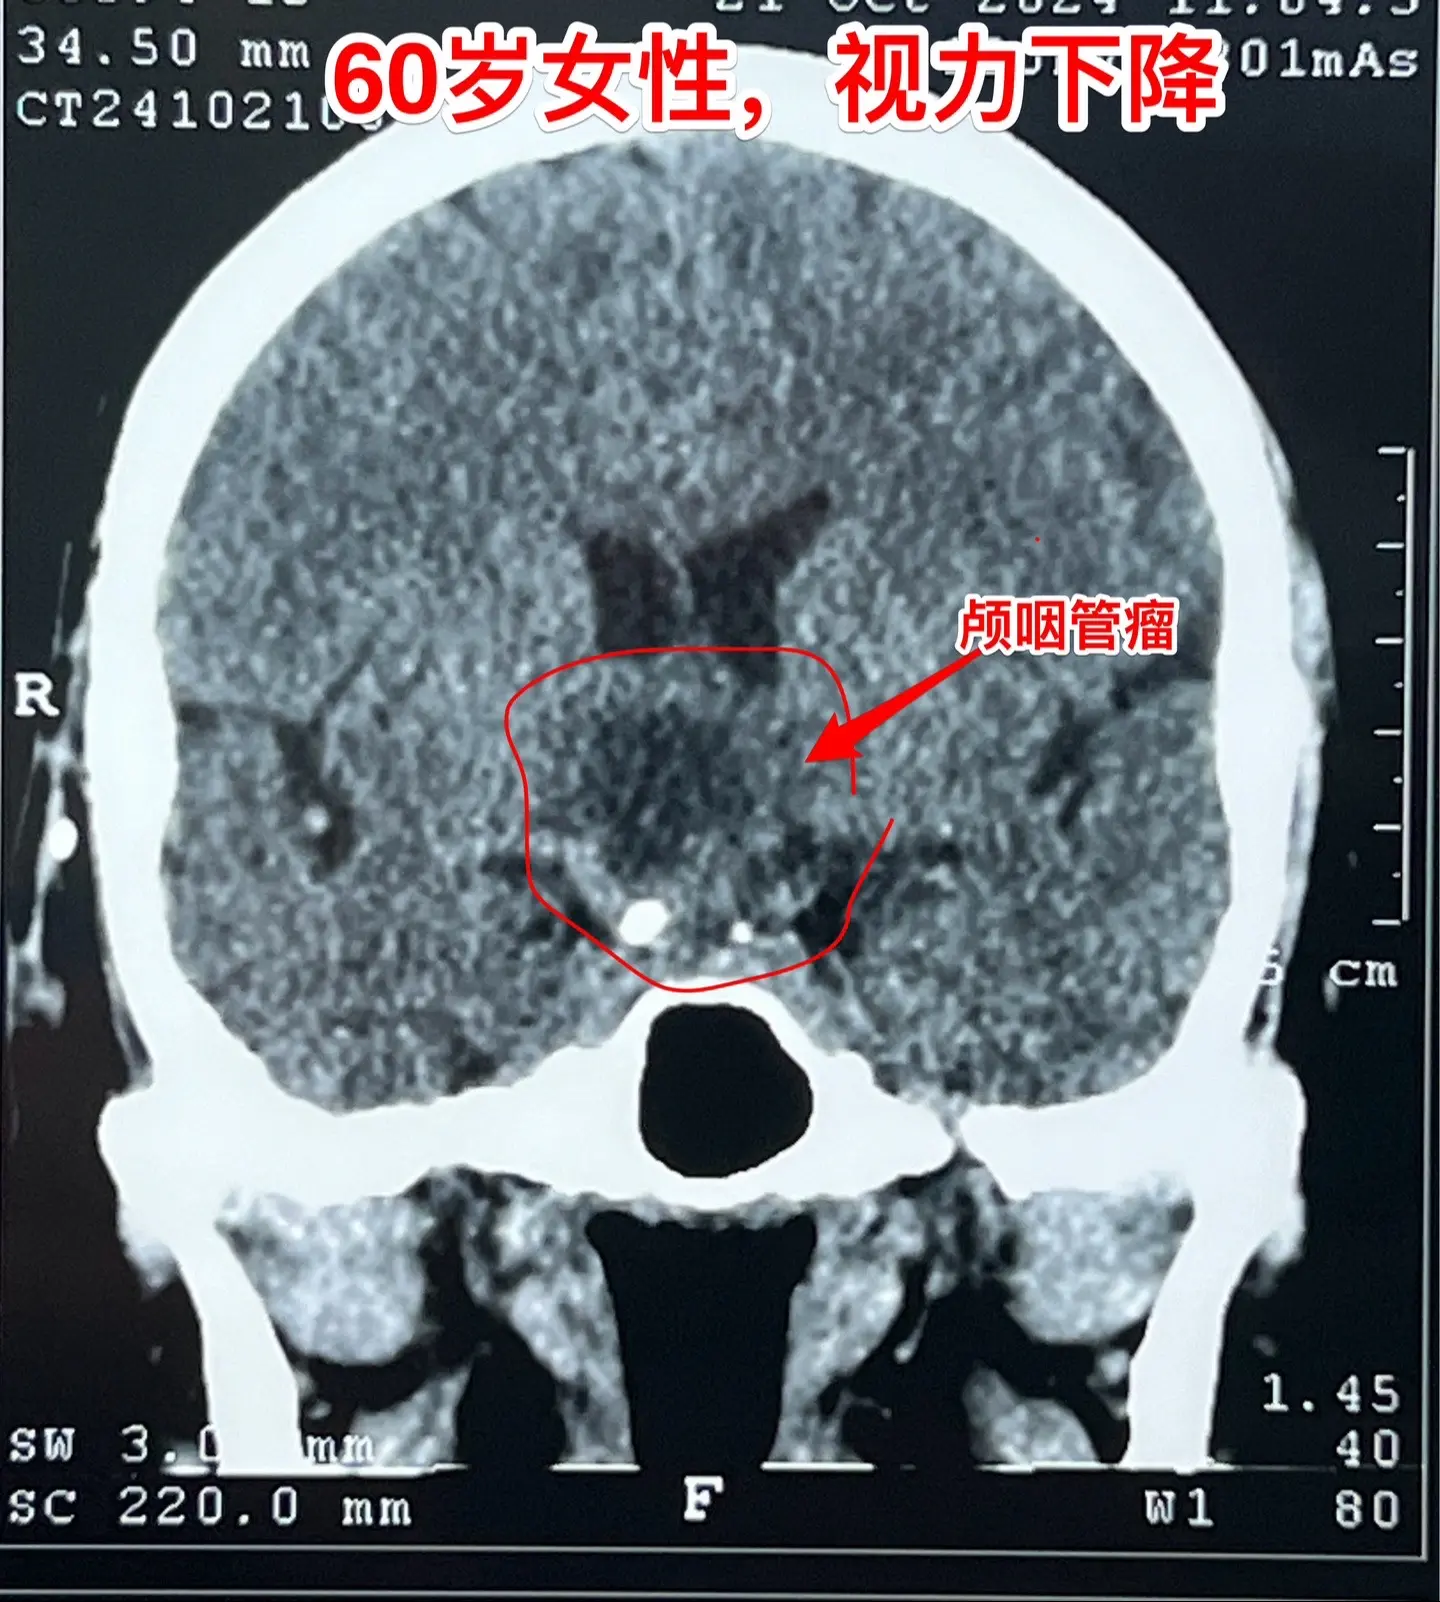

60岁连云港市的老人视力下降⬇️。老人自幼右眼受伤了,右眼视力属于无效...